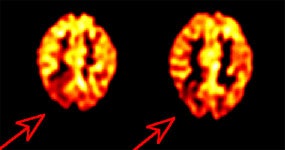

Inter-ictal FDG PET exam: The patient in the case below suffered from intractable drop seizures since the age of 18 months. An MRI was normal. Ictal scalp EEG demonstrated epileptiform activity emanating from the right parietal region. The FDG PET exam revealed a region of hypometabolism (red arrow) in the right parietal lobe. The PET exam guided subdural grid placement with very good correlation. The patient underwent surgical treatment and became seizure free. The exam was performed on an ECAT EXACT HR+ (manufactured by CTI). Case courtesy of Harry Chugani, M.D., Childrens Hospital of Michigan, and CTI PET Systems, Inc. |